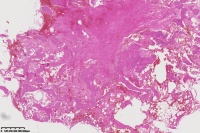

右胫骨内组织,单纯性骨囊肿?

性别

男

年龄

12岁

临床诊断

内生性软骨瘤?骨囊肿?

标本名称

右胫骨内组织

需要结合影像。